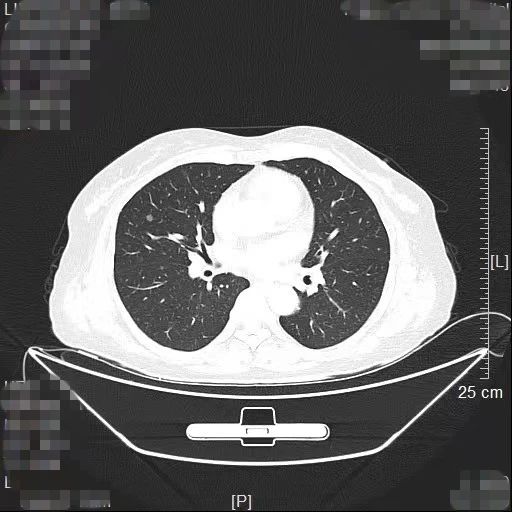

患者林女士今年65岁,长期旅居国外的她在回国后常规体检时查出右肺有2个高危的磨玻璃结节,慕名找到我院胸部肿瘤外科方卫民主任医师。医生团队详细分析了患者的肺部CT及三维重建结果,发现2个结节分别位于右上肺后段边缘及右中肺叶中央,如果直接采用手术切除的方法,要多切除整个右肺中叶,将损失较多的正常肺组织,影响生活质量,得不偿失。

由于患者签证时间将到,无法分次手术,医生团队经过反复讨论,最终为患者量身定做了“针孔消融+单孔微创”的杂交手术方案。首先在医院肿瘤与血管微创介入治疗中心CT引导下为患者右中肺叶结节进行热消融治疗,仅仅一个针眼;接着进行单孔胸腔镜亚肺段切除,仅仅一个3cm大小的切口,术中冰冻病理报告:原位腺癌,疑有浸润。顺利为患者解除了肺部的2个健康隐患。